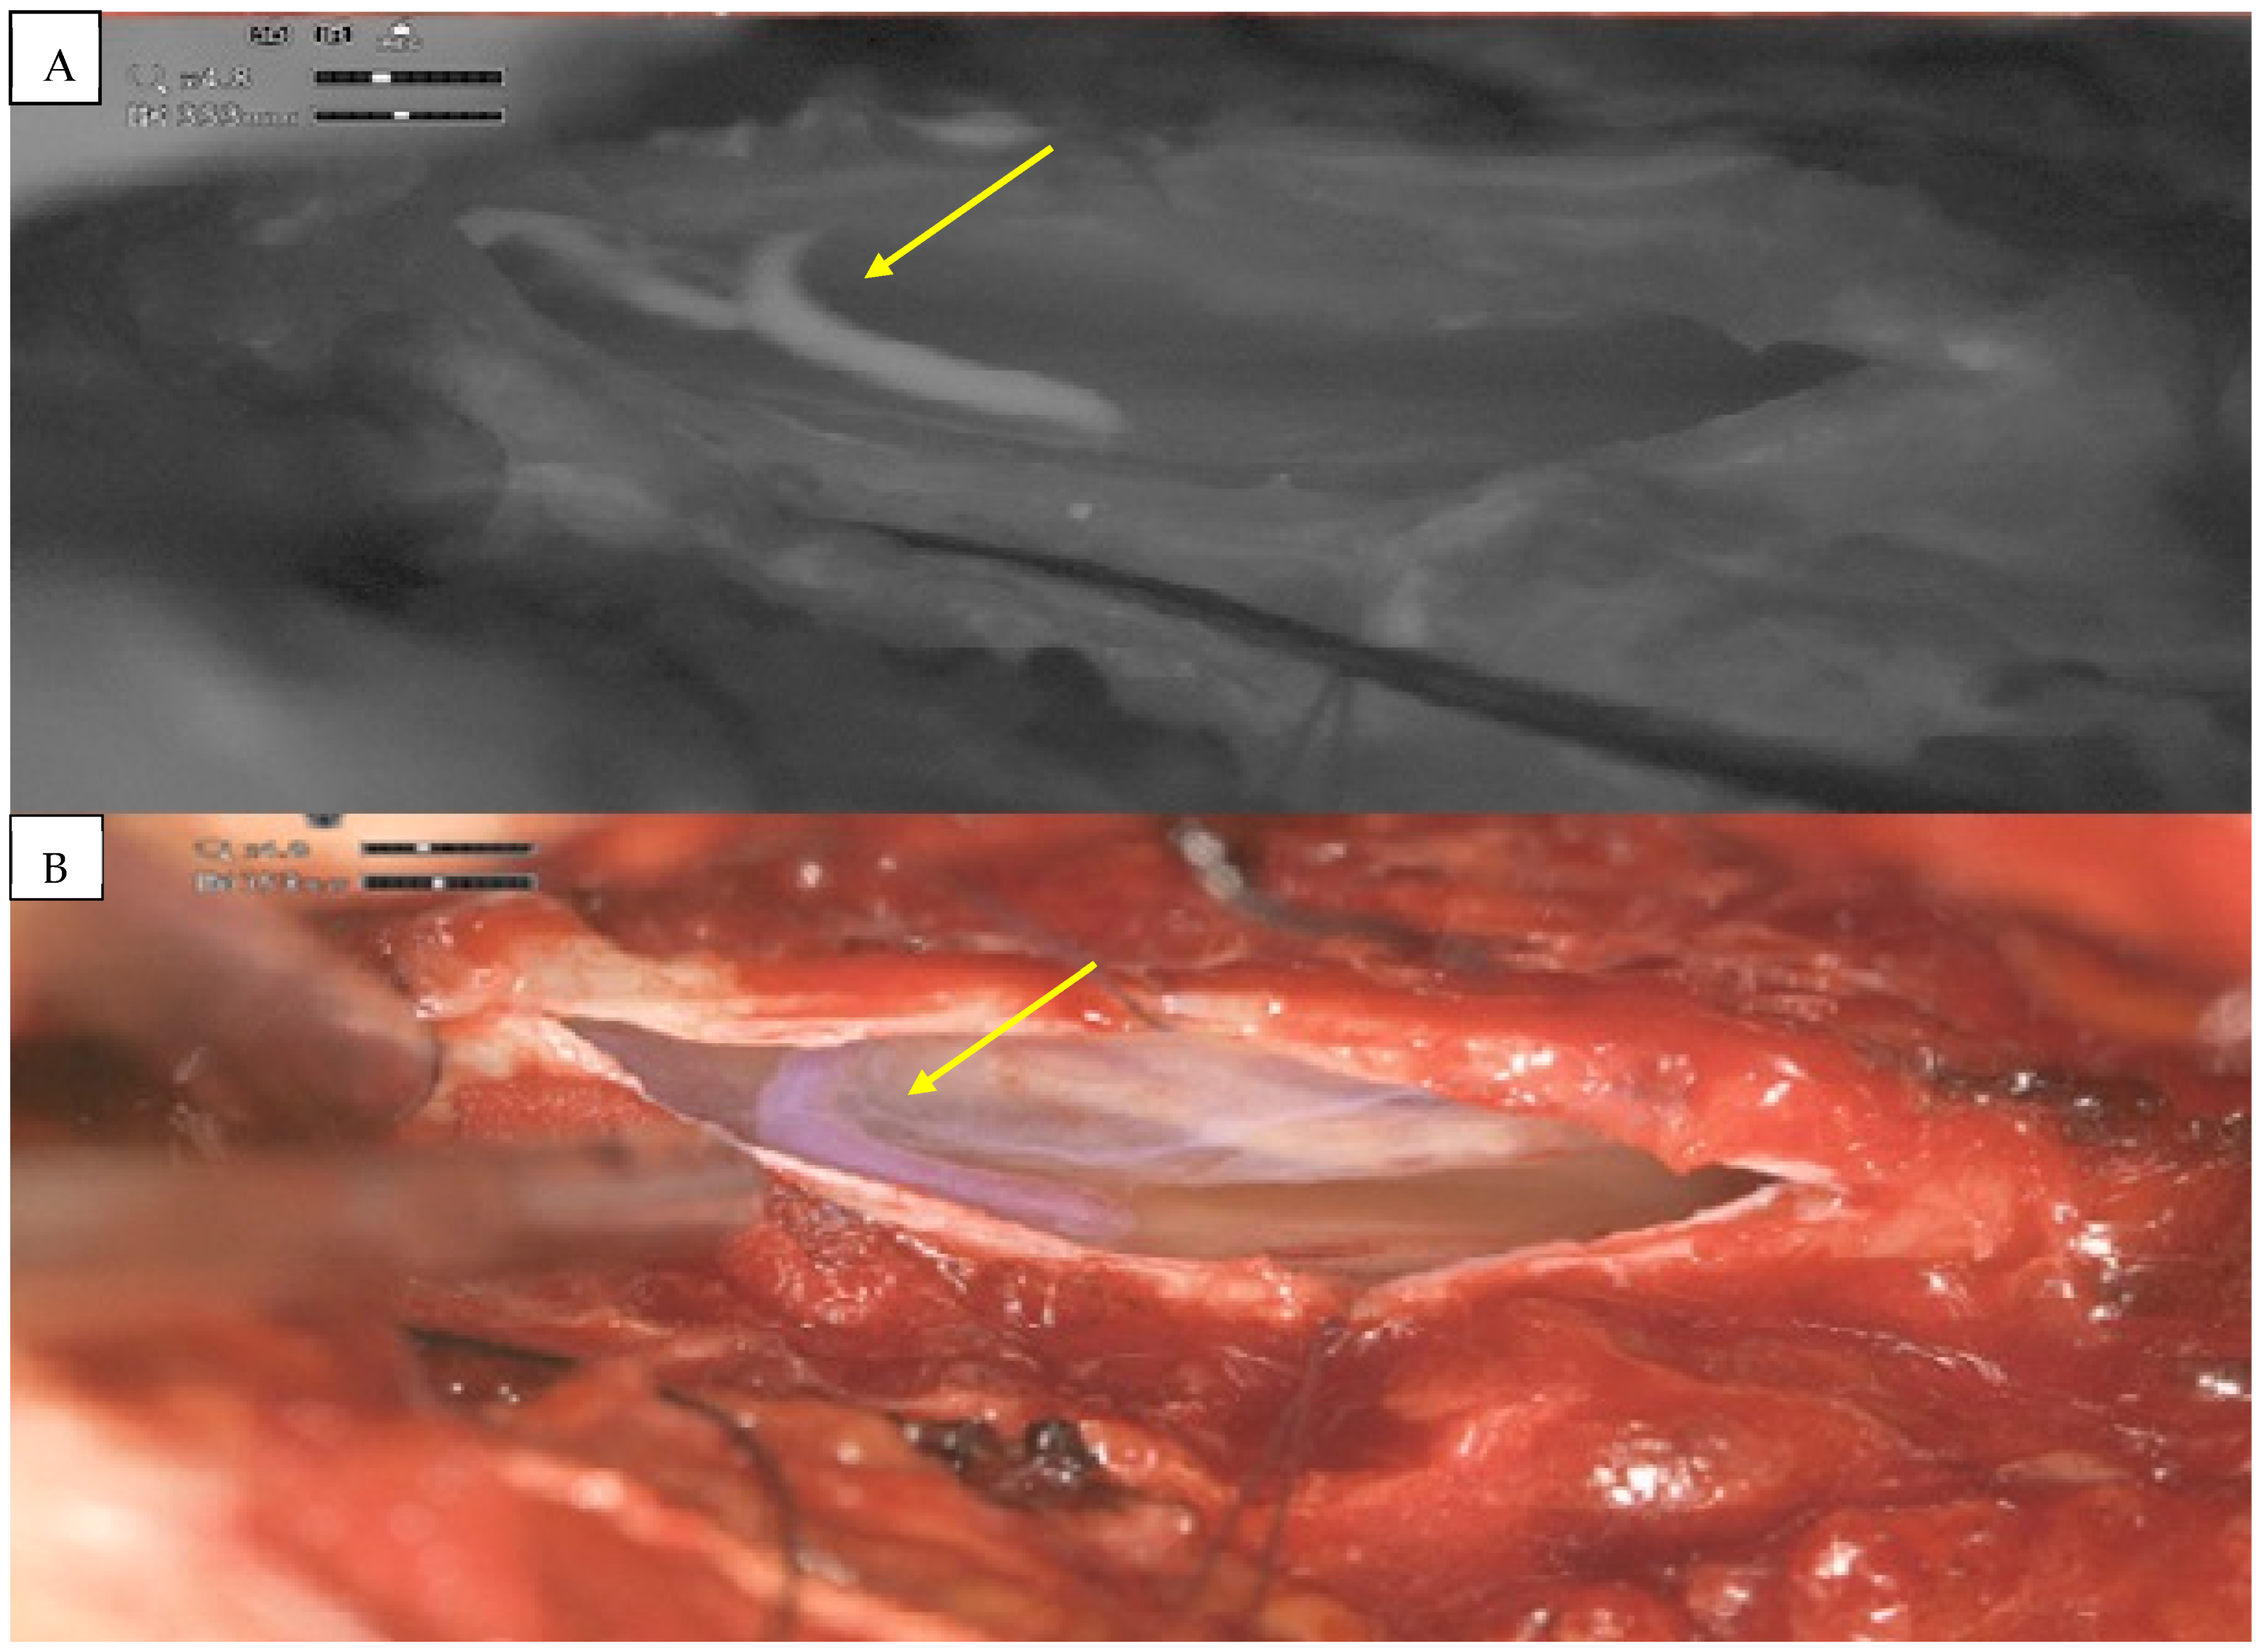

2. Detailed Case Description